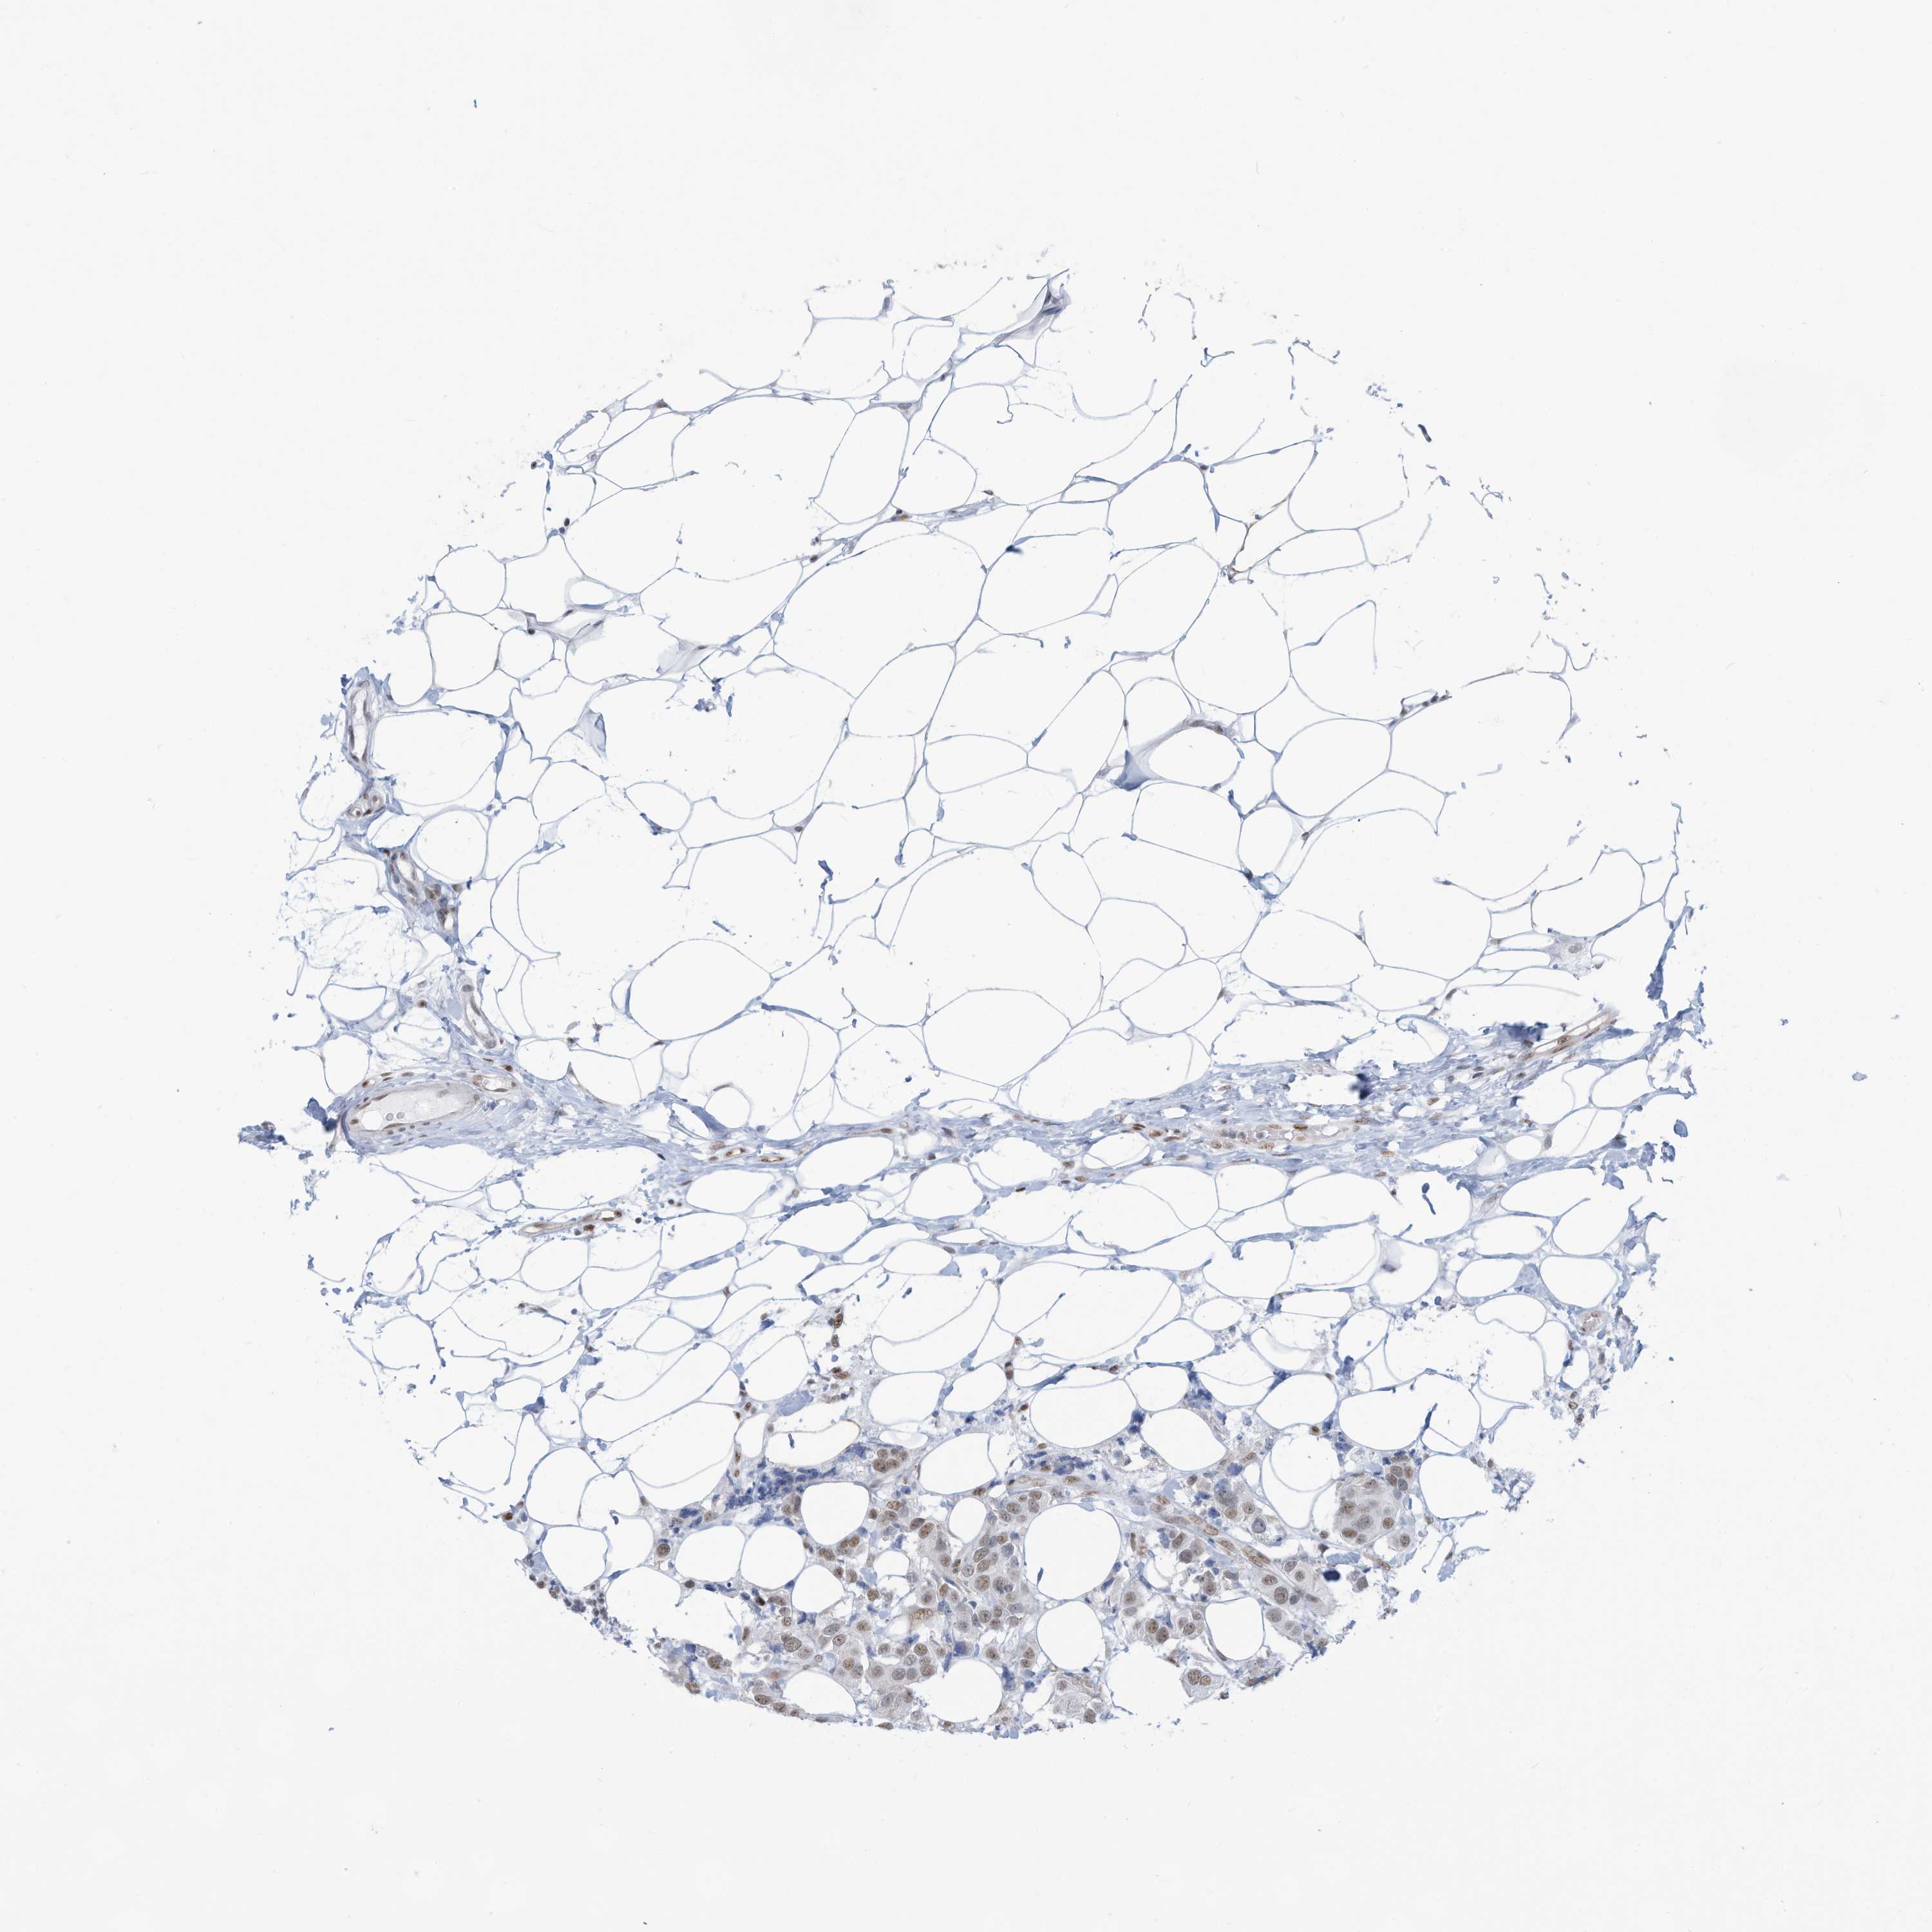

CANCER BREAST CANCER Show tissue menu

BRCA TCGA BRCA VALIDATION PROTEIN EXPRESSION

ANTIBODIES

AND

VALIDATION